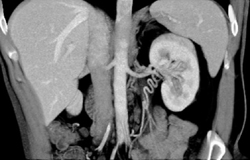

Transitional Cell Carcinoma of the Left Kidney